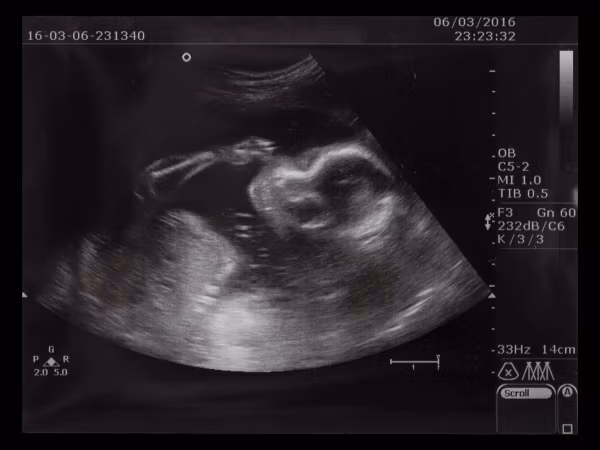

Wird man vom Gynäkologen als Risikoschwangere eingestuft oder die eigene Schwangerschaft als Risikoschwangerschaft bezeichnet bekommt man als werdende Mama einen Schreck. Doch was genau steckt dahinter? Was bedeutet eine Risikoschwangerschaft konkret für dich? Ab wann spricht man von einer Risikoschwangerschaft und was gilt es zu beachten?

Rund bis zu 50% aller Schwangeren werden als risikoschwanger eingestuft. Zu Beginn deiner Schwangerschaft, meistens bei der ersten Schwangerschaftsvorsorge, fragt dein Gynäkologe viele Fragen zu deinem aktuellen Gesundheitszustand, zu Vorerkrankungen und zu vorherigen Schwangerschaft und eventuellen Komplikationen. Die Ergebnisse werden in deinen Mutterpass eingetragen. Darin ist auch eine Seite enthalten, die sich speziell auf Risikoschwangerschaften bezieht. Werden hier ein oder mehrere Kreuzchen gemacht, liegt es im Ermessen deines Arztes, die Schwangerschaft als risikobehaftet einzustufen.

Es gilt für den Frauenarzt immer abzuklären, ob für die Mutter oder das Ungeborene ein gesundheitliches Risiko besteht. Doch keine Sorge, das Feststellen einer Risikoschwangerschaft ist eine reine Vorsichtsmaßnahme. Für dich und dein Baby im Bauch bedeutet es, je nach Risikoeinstufung, dass ihr engmaschiger durchgecheckt werdet und eventuell noch zusätzliche Untersuchungen stattfinden. Gut zu wissen: Die Kosten hierfür werden von deiner Krankenkasse übernommen.

Wird deine Schwangerschaft als Risikoschwangerschaft eingestuft, verändert sich erst einmal gar nichts für dich. Je nach Erkrankung oder Risiko, empfiehlt dir dein Arzt das weitere Vorgehen und rät dir zu Verhaltensempfehlungen. Sind engmaschigere Termine von Nöten, wird dein Gynäkologe dich häufiger einbestellen. Je nach Diagnose werden zusätzliche Tests zur Diagnostik durchgeführt. Das kann ab einem gewissen Alter der Mutter zum Beispiel eine Fruchtwasseranalyse sein oder bei erhöhten Zuckerwerten im Urin ein Diabetestest.